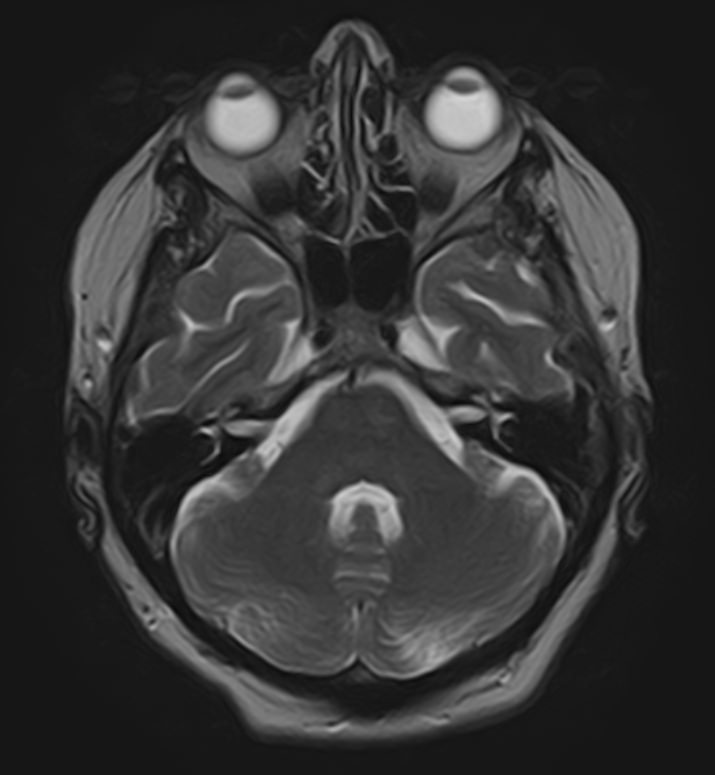

Мосто-мозжечковый угол — это пространство вблизи основания черепа в виде углубления между анатомическими образованиями: продолговатым мозгом, мозжечком и Варолиевым мостом. В этой области располагаются волокна многих черепно-мозговых нервов (например, лицевого, тройничного, преддверно-улиткового), проходят мозговые артерии и многочисленные вены мозжечка.

В мосто-мозжечковом угле часто развиваются воспалительные процессы (арахноидиты) с формированием в дальнейшем арахноидальных кист. Могут выявляться аневризмы расположенных здесь артерий. Но чаще всего в этой области образуются объемные образования, как злокачественные, так и доброкачественные, которые сдавливают расположенные там нервные волокна, кровеносные сосуды и пути ликворного оттока. Наиболее часто встречающаяся опухоль этой области — невринома преддверно-улиткового нерва. В большинстве случаев она имеет доброкачественный характер, развивается, как правило, у людей трудоспособного возраста, преимущественно у женщин. Реже встречаются менингиомы и холестеатомы мосто-мозжечкового угла.

Самым информативным, при этом быстрым и безопасным, методом диагностики опухолей мосто-мозжечкового угла на сегодняшний день является магнитно-резонансная томография с контрастированием. В клинике «Доступная медицина» проводится эффективная диагностика патологии мосто-мозжечкового угла с использованием новейшего томографа TOSHIBA VANTAGE TITAN 1,5 Тесла. Высокая мощность магнитного поля 1,5 Тесла позволяет получить подробное изображение этой труднодоступной для диагностики области в различных плоскостях.

Контрастирование проводится контрастным веществом на основе солей гадолиния (химический элемент, относящийся к редкоземельным металлам). Применяемый контрастный препарат накапливается в патологическом очаге, за счет чего при сканировании усиливается его яркость изображения. Это дает возможность выявить опухоли малых размеров (до 3 мм) и назначить своевременное лечение. Кроме того, контраст заполняет просвет сосудов, благодаря чему на снимках появляется детальное изображение сосудистой сети. Это позволяет диагностировать патологическую извитость, аневризмы, мальформации, при вазоневральном конфликте — зоны сдавления черепно-мозгового нерва кровеносным сосудом.